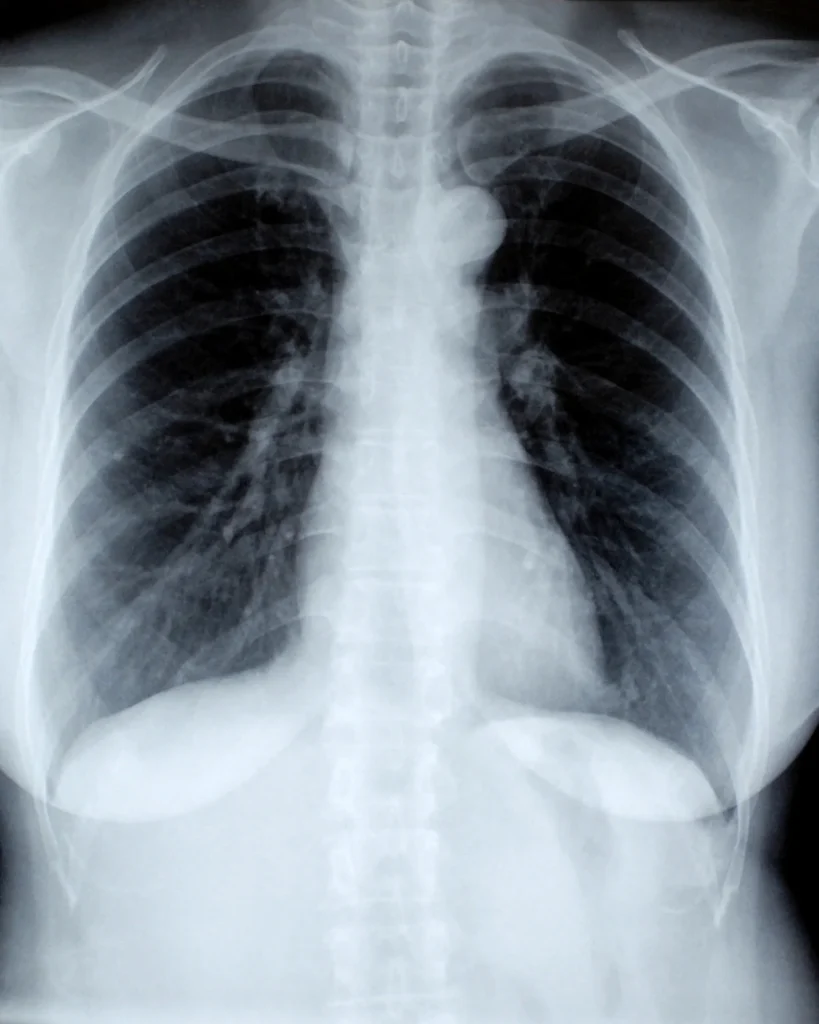

La angiotac de tórax es un procedimiento que facilita la visualización de los vasos sanguíneos del pecho y la parte superior del abdomen. A través de un medio de contraste, permite una visión más precisa de la anatomía arterial torácica.

La angiotac de tórax es un examen que permite detectar diversas patologías vasculares como aneurismas arteriales y venosos, enfermedad obstructiva arterioesclerótica y anomalías vasculares congénitas.